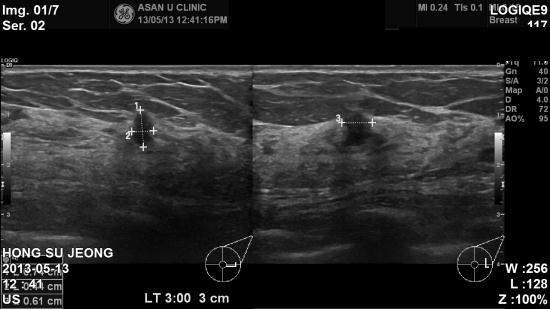

건강검진 진행 후 유방촬영 상 유방 소견으로 내원하신 64세 여성분이십니다.

본원 초음파상 좌측 3시방향 길게 자란 0.7cm 혹있어 조직검사 시행하였습니다.

결과상 유방암으로 진단 되었습니다.